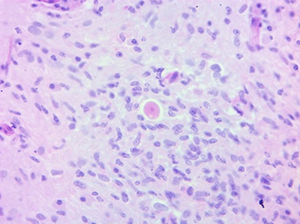

Figura 4. Tinción de Hematoxilina y Eosina.

El diagnóstico histopatológico definitivo de EGA fue indefinido, atribuido a Acanthamoeba spp. o B. mandrillaris, la dificultad bajo microscopía de luz crea la necesidad de realizar PCR o inmunofluorescencia.